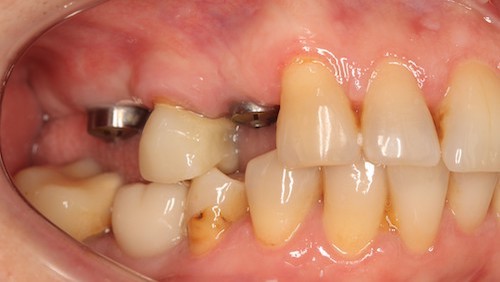

Пациентка обратилась с проблемой отсутствия зубов в боковом отделе и трудностями при пережевывании пищи. При этом решать вопросы с эстетическими нюансами фронтальных зубов пациентка совершенно не хотела, поэтому я и мои коллеги сконцентрировали свое внимание на задних зубах.

Ляшев Илья Николаевич успешно провел имплантацию 5 ед системы Astra Tech с одномоментным наращиванием костной ткани в области отсутствующих зубов. после приживления имплантов были выполнены временные коронки, а затем и постоянные как на имплантах, так и на собственных зубах. Еще предстоит работа с верхним зубным рядом, но уже сейчас получилось повысить качество пережевывания пищи.

После